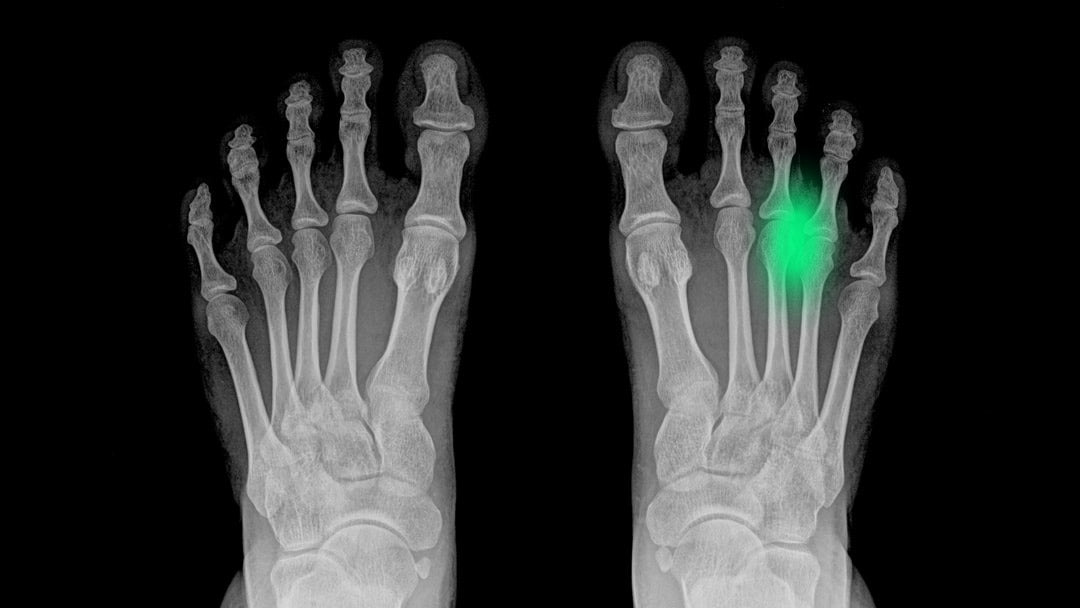

Morton-Neurom: Ursachen, Symptome und Behandlung

Das Morton-Neurom ist eine schmerzhafte Erkrankung, die durch die Kompression eines Nervs zwischen den Zehen, insbesondere zwischen dem dritten und vierten, verursacht wird. Erfahren Sie mehr über ...